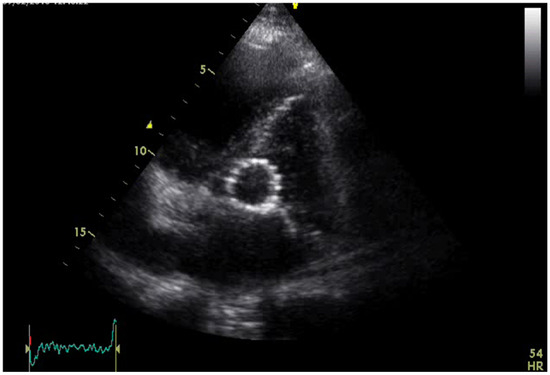

Background and Clinical Significance: Concomitant severe aortic stenosis (AS) and abdominal aortic aneurysm (AAA) in elderly patients presents a significant therapeutic challenge. While transcatheter aortic valve replacement (TAVR) and endovascular aneurysm repair (EVAR) have become established minimally invasive treatments for high-risk patients, [...] Read more.

Background and Clinical Significance: Concomitant severe aortic stenosis (AS) and abdominal aortic aneurysm (AAA) in elderly patients presents a significant therapeutic challenge. While transcatheter aortic valve replacement (TAVR) and endovascular aneurysm repair (EVAR) have become established minimally invasive treatments for high-risk patients, simultaneous management of both conditions remains rare. Case Presentation: We report the first documented case in Serbia of a simultaneous TAVR and EVAR in a 75-year-old male with severe symptomatic AS and AAA. The patient had a history of hypertension, diabetes mellitus, atrial fibrillation, prior radiofrequency pulmonary vein ablation, and pacemaker implantation. Echocardiography demonstrated severe AS with a transvalvular gradient of 116/61 mmHg, an aortic valve area of 0.6 cm2, and a left ventricular ejection fraction of 30–35%. Coronary angiography revealed 50–60% stenosis of the right coronary artery. Following evaluation by a multidisciplinary Heart and Vascular Team, a combined procedure was performed under general anesthesia via bilateral femoral access. TAVR with a Medtronic Evolut R valve was successfully deployed, followed by EVAR with satisfactory stent graft positioning and angiographic results. The patient’s postoperative course was uneventful, and he was discharged on the ninth day. At six-month follow-up, echocardiography showed optimal valve function, and CT identified a type II endoleak, which was managed conservatively. Conclusions: This case demonstrates the feasibility and safety of simultaneous TAVR and EVAR in a high-risk elderly patient, emphasizing the importance of careful preoperative planning and a coordinated multidisciplinary approach. Further studies are warranted to establish standardized guidelines for the management of patients with coexisting severe AS and AAA. Full article